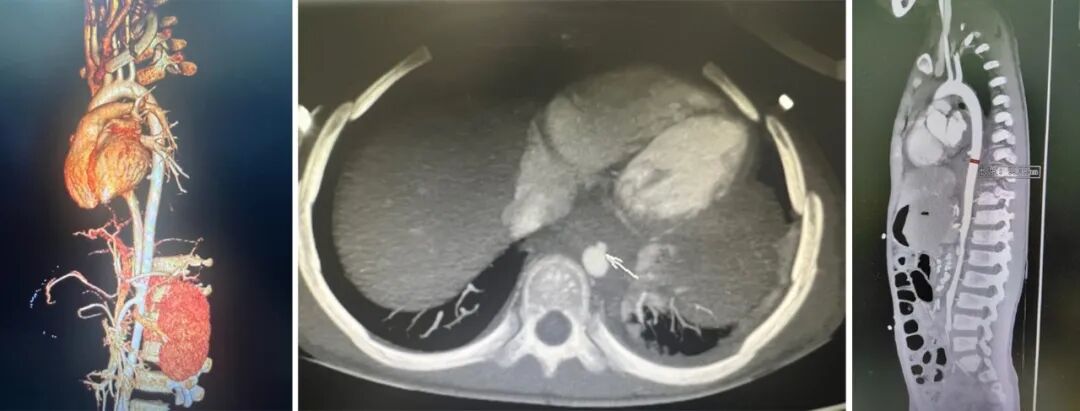

术前诊断:主动脉食管瘘,胸降主动脉假性动脉瘤,食管周围淋巴瘤术后。

术前主动脉CTA:胸降主动脉局部假性动脉瘤。

gore医疗怎么样How I Do It | 张雷杨教授团队:Gore VBX用于儿童主动脉食管瘘治疗一例分享_https://www.jmylbn.com_新闻资讯_第3张